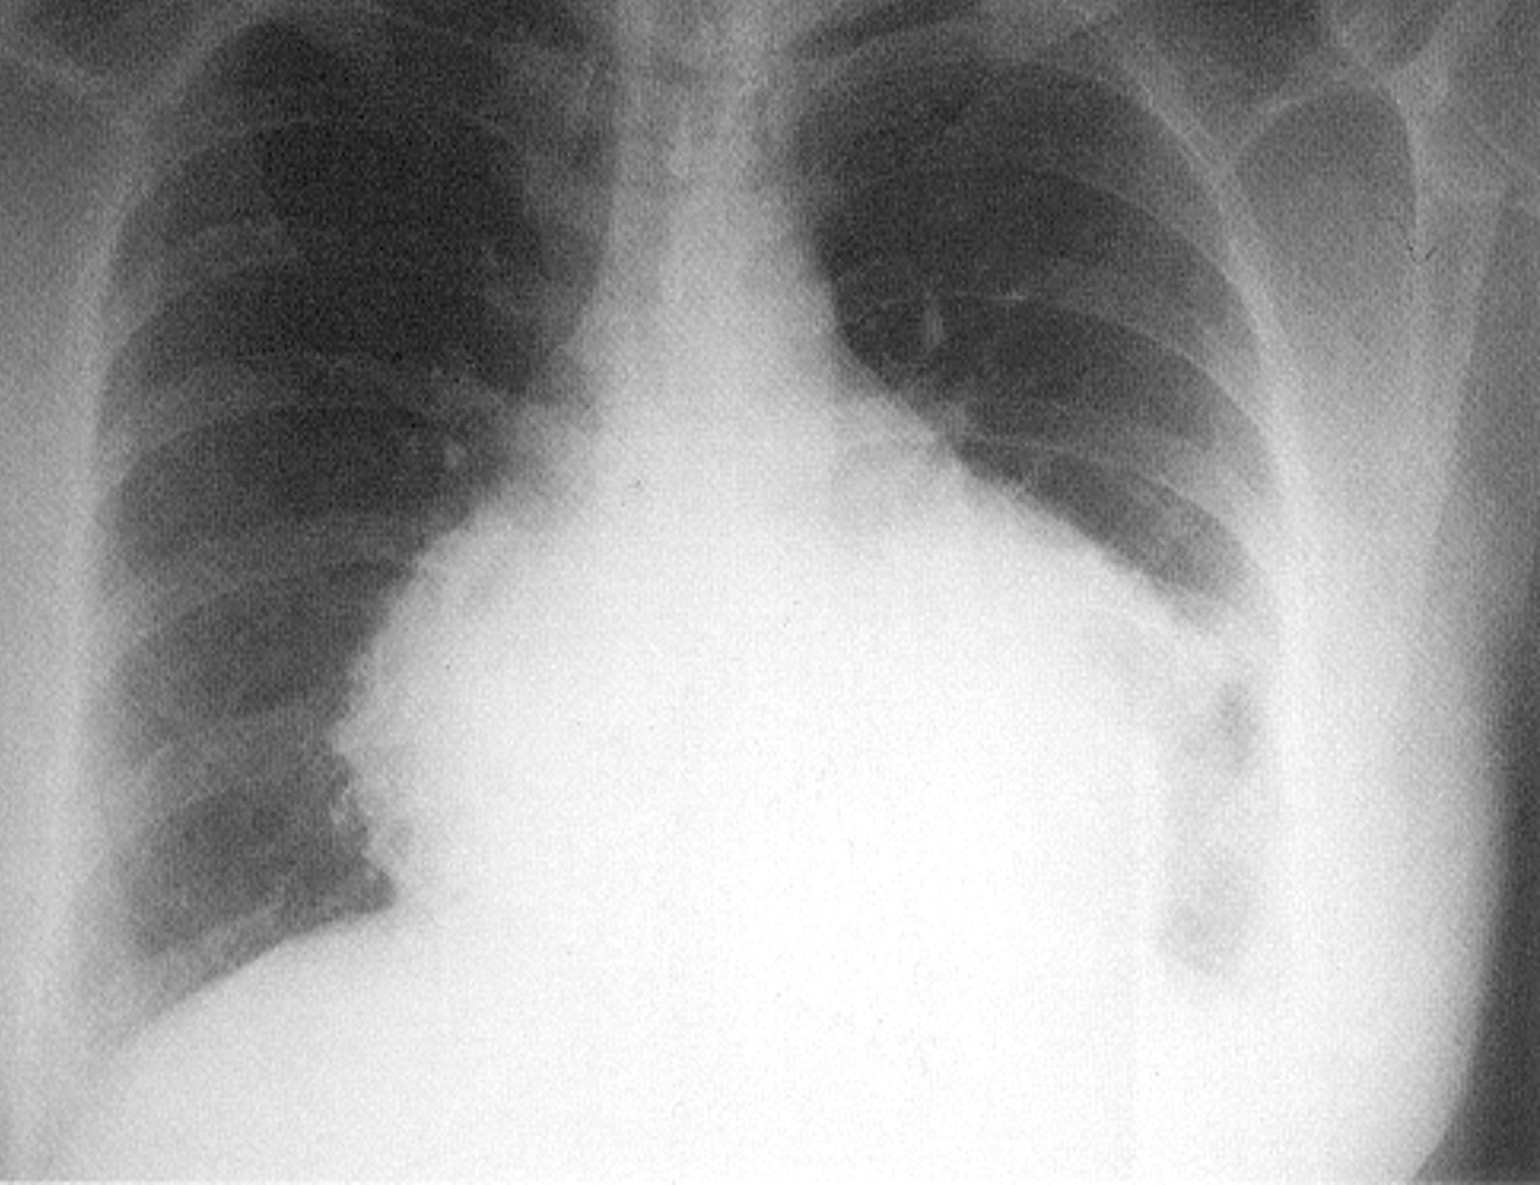

B

2

Pericarditis with effusion Acute pericarditis